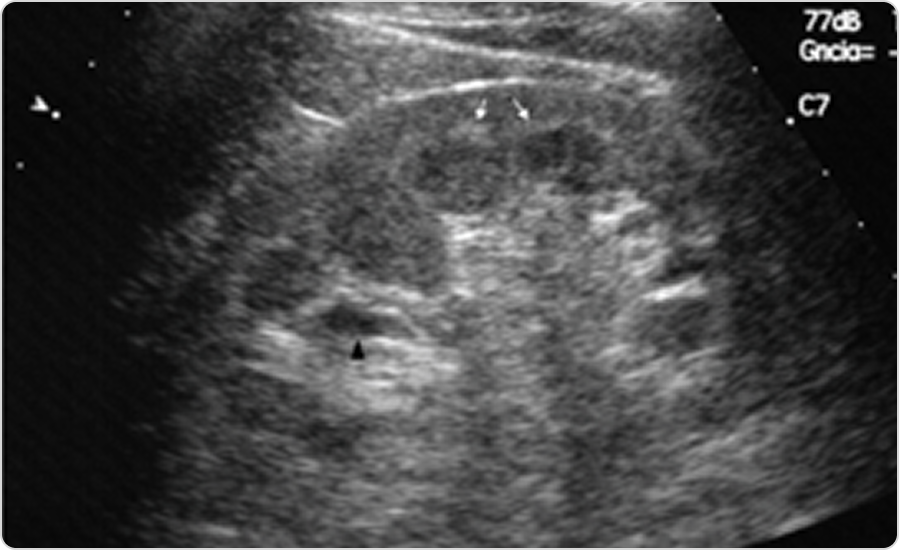

Фабри ауруы кезіндегі бүйректің ультрадыбыстық кескініФабри ауруы кезіндегі бүйректің ультрадыбыстық кескіні

2-сурет. Құрсақ қуысының УДЗ-сы: Фабри ауруы бар пациенттің сол жақ бүйрегінің қыртысты-милық гиперэхогенділігі және парапельвикалық кисталары бар қиғаш кесіндісі.

Дереккөзден бейімделген: Azancot MA, Vila J, Domínguez C, Serres X, Espinel E. Multiple parapelvic cysts in Fabry disease. Nefrología. 2016;36(5):533–536. Open Access.31

Фабри ауруы бар пациенттердің 50 %-ында бүйрек синусының кисталары немесе парапельвикалық кисталар болады32